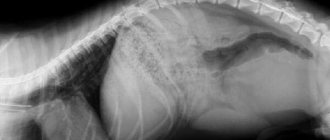

Вторая болезнь, относящаяся к разряду наследственных, представляет для жизни собаки несравнимо большую угрозу. Речь идет о дисплазии межпозвоночных дисков. Достаточно высокая частота возникновения этого заболевания связана с характерным строением тела таксы. Проблемы с межпозвоночными дисками могут привести к ущемлению тела спинного мозга, деформации нервных стволов и, как следствие, параличу. Статистика показывает, что наиболее критический возраст для появления болезни – 5-7 лет, хотя известны и более ранние случаи диагностирования этого заболевания. Очень важно в этой связи строго контролировать интенсивность физических нагрузок и правильно кормить животное, ни в коем случае не допуская набора лишнего веса. Это позволит в значительной степени уменьшить нагрузку на позвоночник.